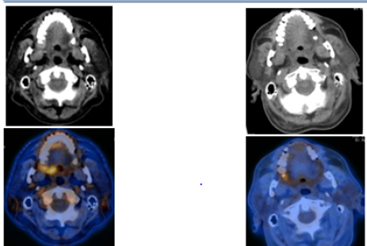

68yr old male who underwent Right kidney transplant for non-functional bilateral kidney presented in with carcinoma of soft palate cT2N0M0.PET CT scan without contrast revealed 1x2x2.7cm soft tissue density mass in the right soft palate and perialveolar region in right upper third molar suggestive of carcinoma soft palate extending to alveolus with suv 3.5 as shown in Figure 2. Biopsy revealed squamous cell carcinoma, for which he was treated with Radiation using Intensity modulated radiation therapy (IMRT) to the dose of 70Gy in 35 fraction over 7 weeks with weekly 5 fraction. In Figure 1 the 70Gy dose distribution was shown in colour wash over the gross disease. Chemotherapy was not considered because of renal compromise and it was stage 2 disease. Patient had complete response of the disease and was on regular follow up.

Figure 1 Dose distribution of the soft palate and Alveolus.

Figure 2 Pretreatment and post radiation treatment PET CT.